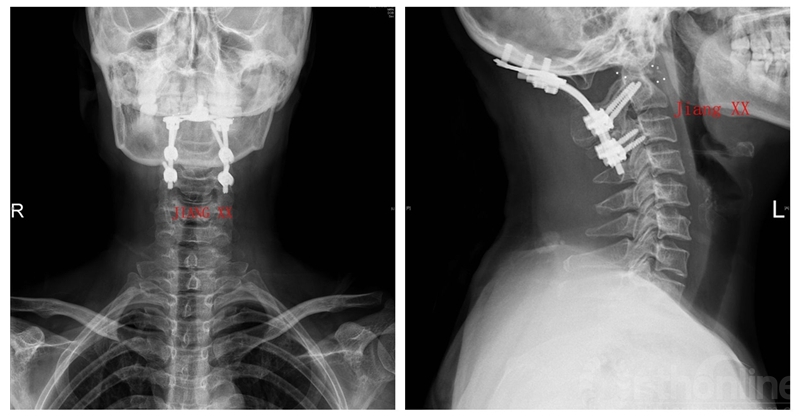

术后X线